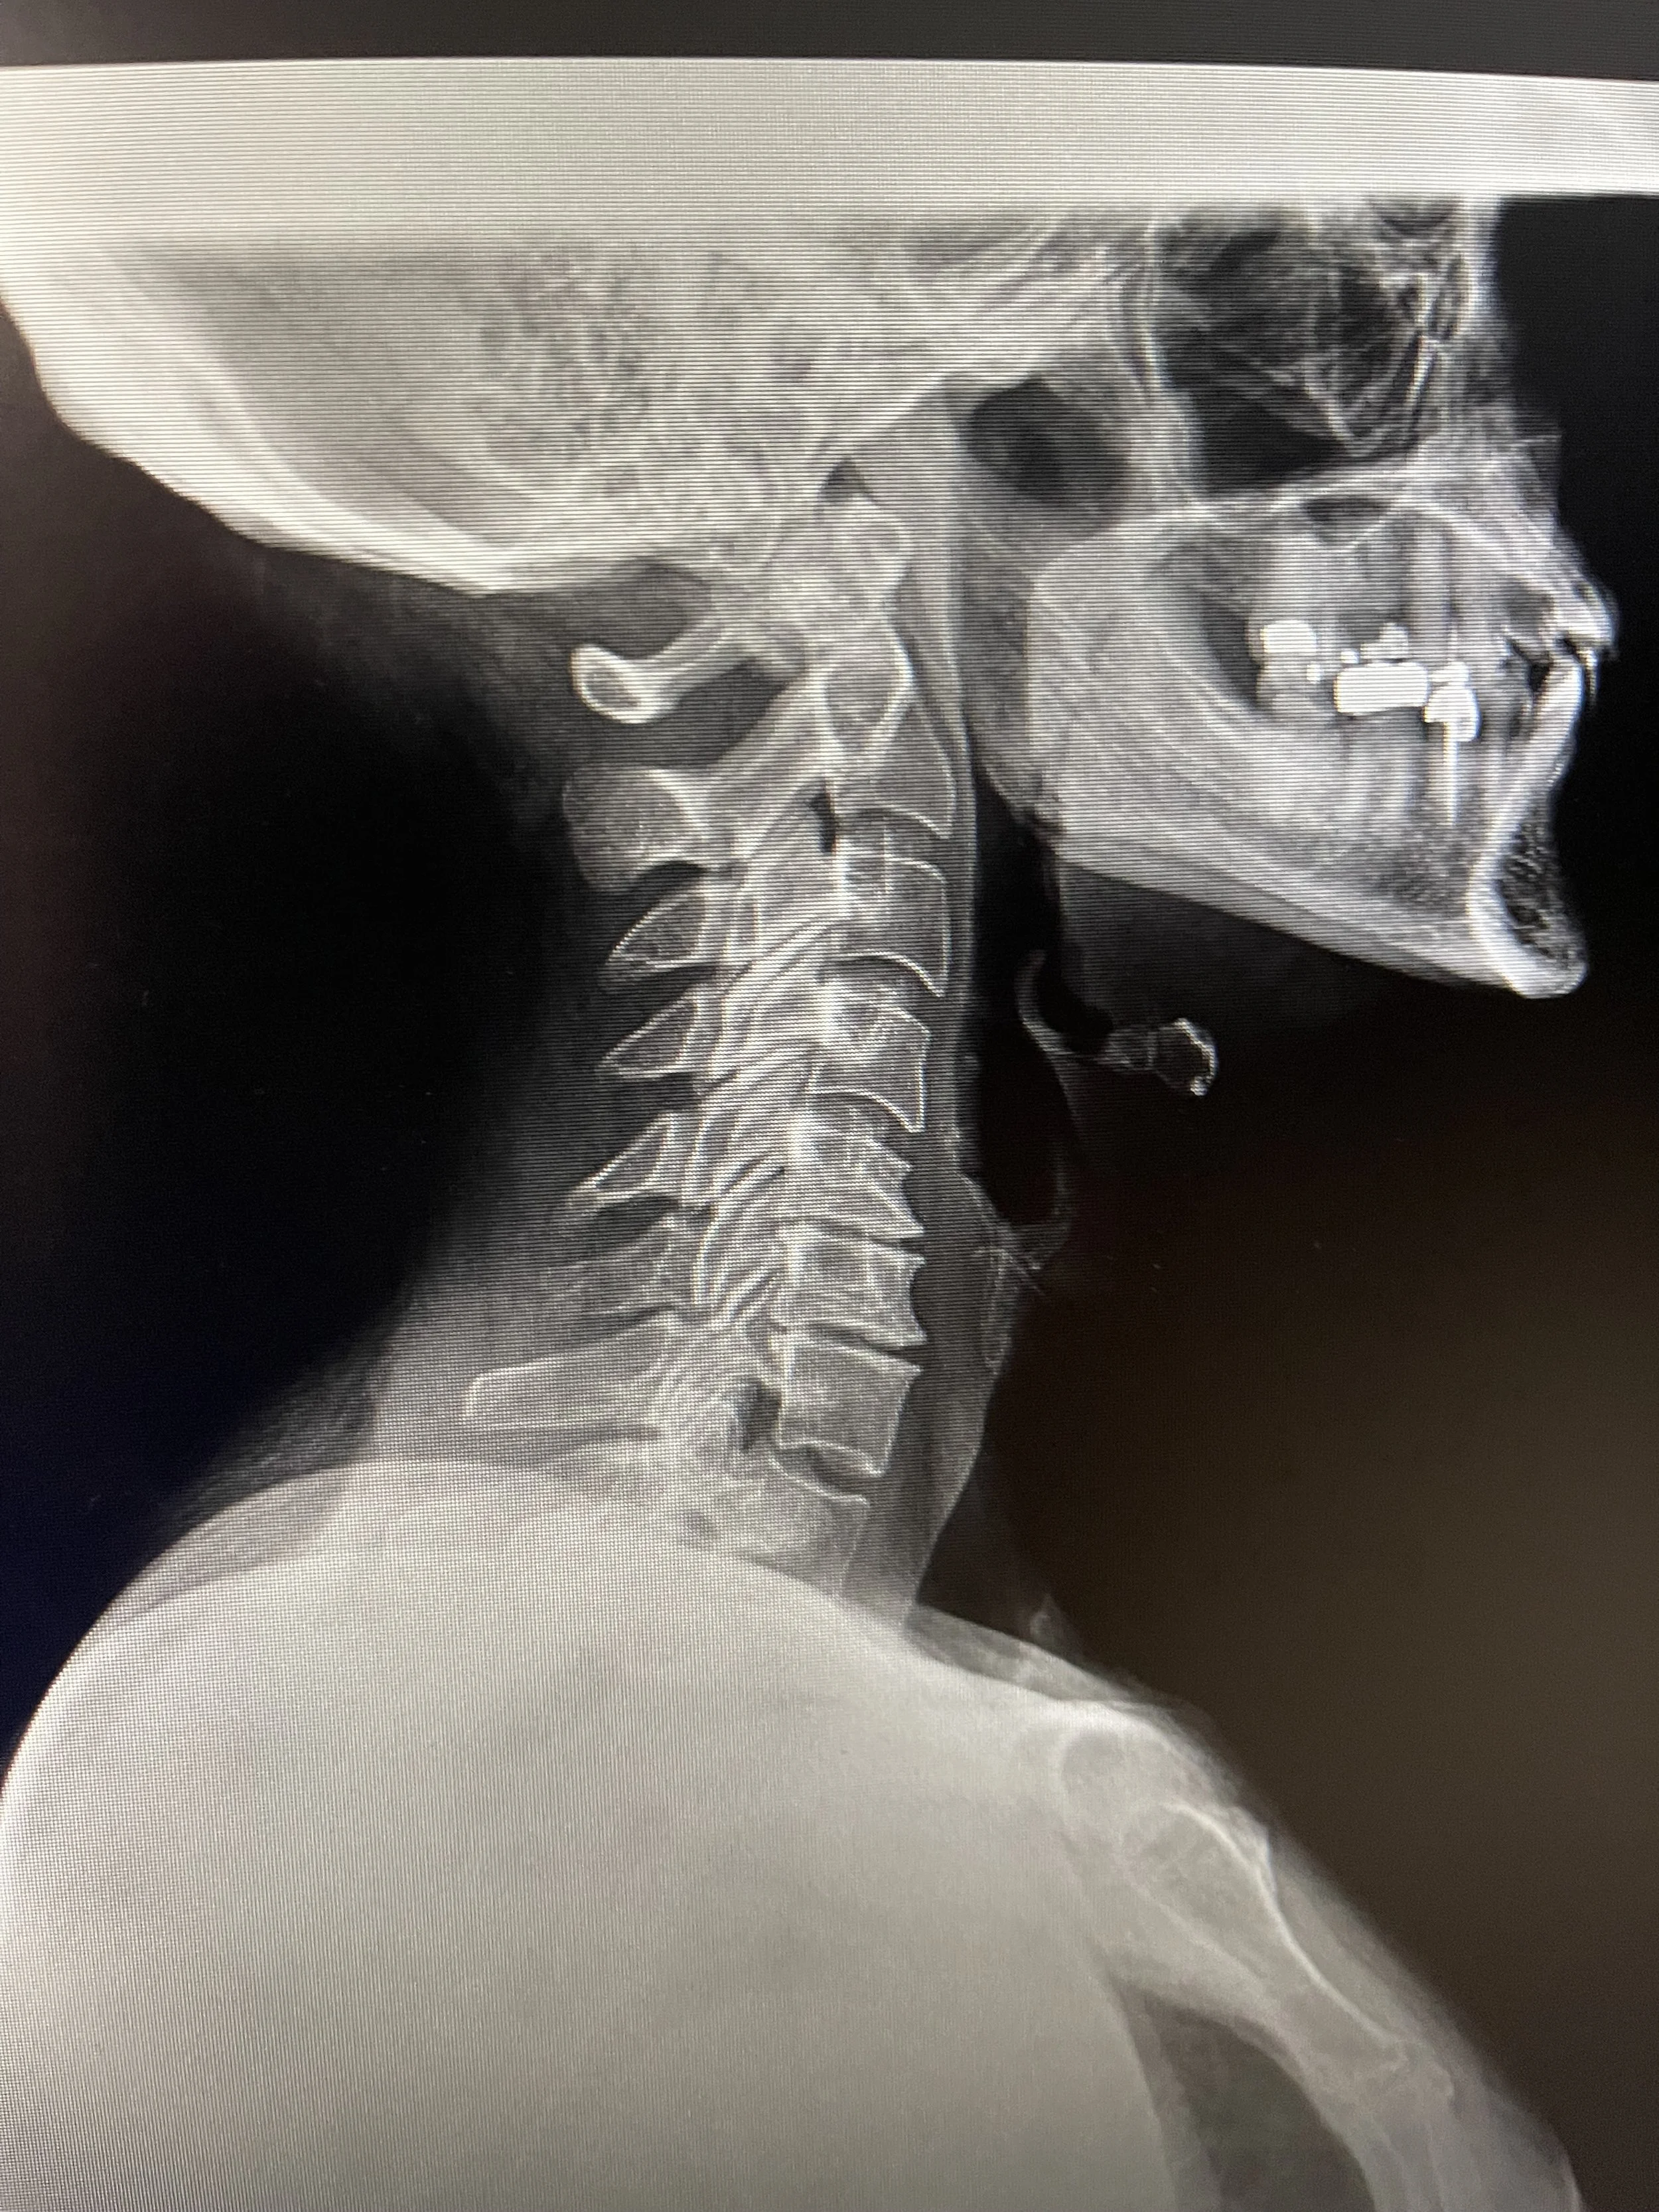

REPORT EXAMPLE